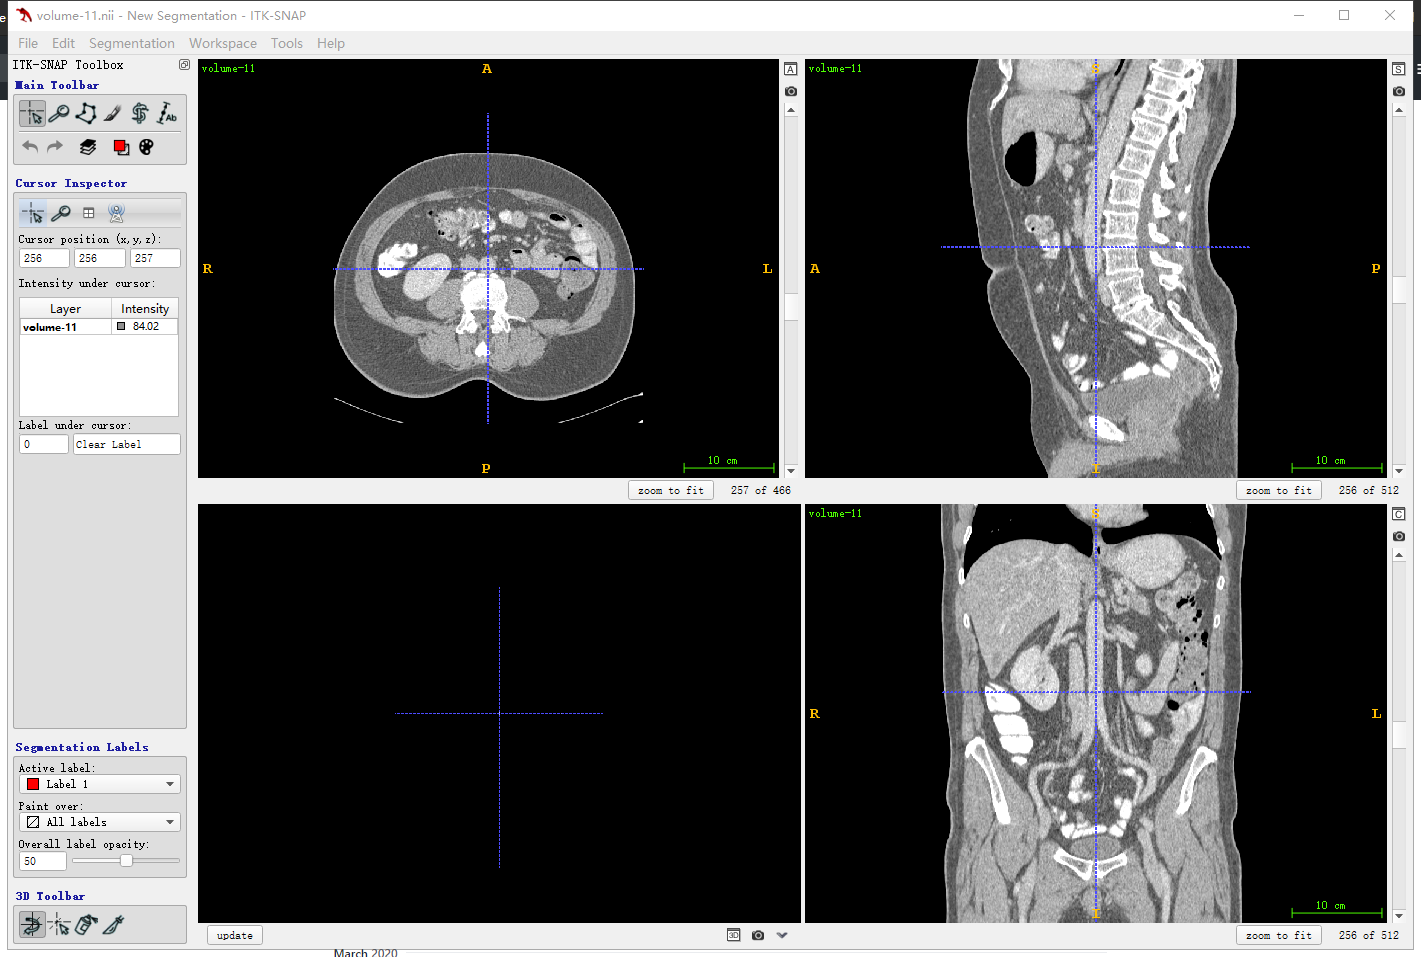

ITK-snap界面

首先要明确一下和人体对应的方向,其中三个窗口对应三个切面,对应关系如下图所示,按照字母索引即可。例如,左上图对应R-A-L-P这个面,是从脚底往头部方向看的切面(即z方向),另外两张类似。

红色切面为矢状面,紫色切面为冠状面,绿色切面为横断面